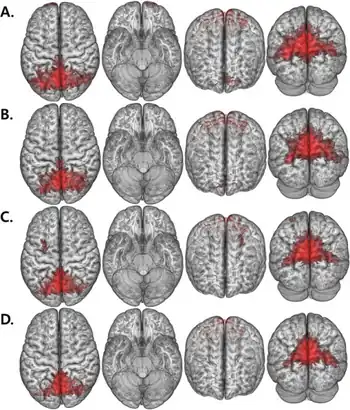

HIV is associated with pathological changes in mainly subcortical and fronto-striatal areas of the brain, including the basal ganglia, deep white matter, and hippocampal regions. Neuroimaging studies of HIV patients indicate that significant volume reductions are apparent in the frontal white matter, whereas subcortically, hypertrophy is apparent in the basal ganglia, especially the putamen.[17] Moreover, the results of some studies suggest loss of brain volume in cortical and subcortical regions even in asymptomatic HIV patients and patients who were on stable treatment.[27] A recent longitudinal study of a small representative cohort of HIV-positive patients on stable medication regiments suggests that this cortical atrophy is progressive, and is in part related to nadir CD4.[28] Cerebral brain volume is associated with factors related to duration of the disease and CD4 nadir; patients with a longer history of chronic HIV and higher CD4 nadir loss present with greater cerebral atrophy.[27] CD4 lymphocyte counts have also been related to greater rates of brain tissue loss.[29] Current factors, such as plasma HIV RNA, have been found to be associated with brain volumes as well, especially with regards to basal ganglia volume[27] and total white matter.[30] Loss of cortical grey matter oligodendrocytes might also contribute to the symptomatology.[31]

Neuroimaging studies

A study by Melrose et al. (2008) examined the integrity of the fronto-striatal circuitry that underlies executive functioning in HIV. Participants in the study were diagnosed with HIV three months to sixteen years before the study. Ten out of eleven patients were on antiretroviral medication and none scored within the demented range on the HIV Dementia Scale. It was found that HIV+ patients showed less activity within the ventral prefrontal cortex (PFC) and left dorsolateral PFC. There was reduced connectivity between the left caudate and ventral PFC and between the left caudate and dorsolateral PFC compared to healthy controls. Additionally, there was hypoactivation of the left caudate in the HIV+ patients. In the control group, there was correlation between caudate activity and executive functioning as shown by performance on neuropsychological testing. Further analysis of the pathways in the HIV+ group involving left caudate showed reduced functional connectivity between the left caudate and globus pallidus (basal ganglia output nucleus). This dysfunction with the basal ganglia and PFC may explain the executive function and semantic event sequencing task impairments noted in HIV+ patients included in this study.[34]

The study by Melrose et al. (2008) also investigated parietal activation. It was found that anterior parietal activation in HIV+ patients was slightly anterior to that in control participants, which follows the idea that HIV causes a reorganization of the attention network leading to cognitive impairments. Additionally, the anterior parietal activity showed a relationship with caudate functioning, which implicates a compensatory mechanism set forth when damage to the fronto-striatal system occurs.[34]

Overall, the study by Melrose et al. (2008) showed that HIV in the brain is associated with cognitive impairments. Damage to the fronto-striatal system may underlie cognitive problems including executive function and sequencing tasks.